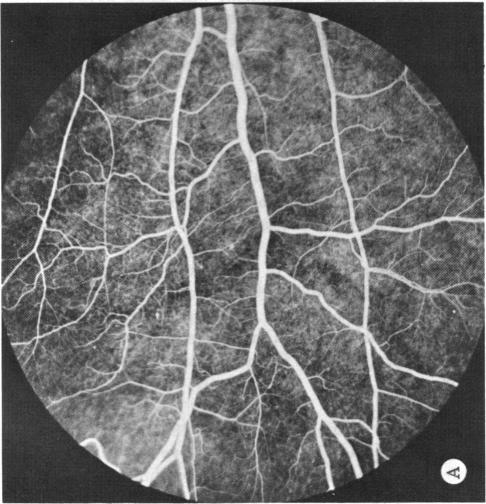

Coats' disease and congenital vascular retinopathy.

Trans Am Ophthalmol Soc. 1976;74:365-424.